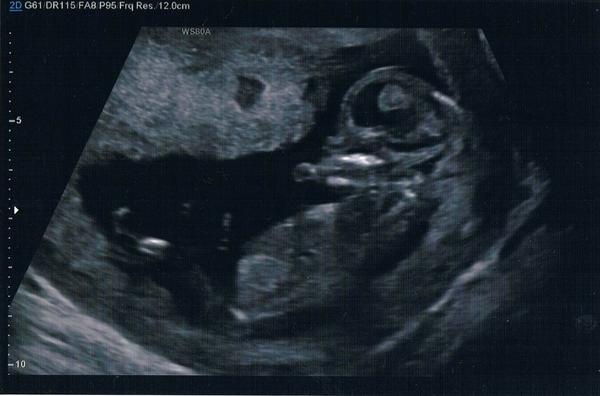

Je to holčička nebo chlapeček? Foto ultrazvuku

@arnicka Asi holčička bych rekla

@pampeliska1 tipuji chlapecka..u holcicky by zrejme bylo videt "kavove zrno" .-)